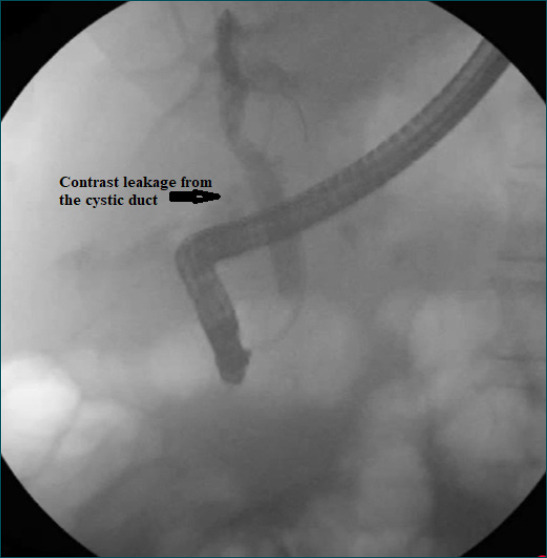

Background: Cystic stump leakage is the most common cause of bile leakage following cholecystectomy, representing a significant postoperative complication that requires prompt intervention. Currently, endoscopic treatment is the preferred management approach. This study aims to identify factors influencing the success of endoscopic therapy for cystic stump leaks by analyzing cases treated at our institution.

Methods: Thirty-seven patients who underwent endoscopic retrograde cholangiopancreatography (ERCP) for cystic stump leakage were included in this study. Patient demographics, associated complications, and length of hospital stay were analyzed.